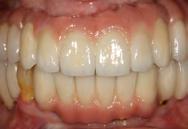

Estudios intraorales de inicio

En las fotografías ( Figura 2 ) se observa clase III esquelética, hiperdivergente, la clase III molar derecha y clase que no está determinada, la molar izquierda, clase canina derecha III, clase II canina izquierda, (Figura 3) con la ausencia de los OD 17, 15, 16, 36, 37, 47, el 23 está retenido en palatino, el overjet y overbite están disminuidos, con la línea media inferior desviada, la paciente refiere que ya le habían realizado una cirugía de Lefort IV antes de llegar al CESO.

Vista oclusal las formas de arco oval superior es indeterminada al igual que la superior e inferior (Figura 4)

Figura 2. Frente inicio. Figura 3. Izquierda y derecha intraoral de inicio.

se ve la malposición, apiñamiento con la ausencia de órganos dentarios.

Figura 4. Vista arcadas superior e inferior. Figura 5. Rx Panorámica.

Progreso, final, circunferencial superior con cinturón vestibular y premolares de stock, circunferencial inferior con molar de stock (Figura 6-8).